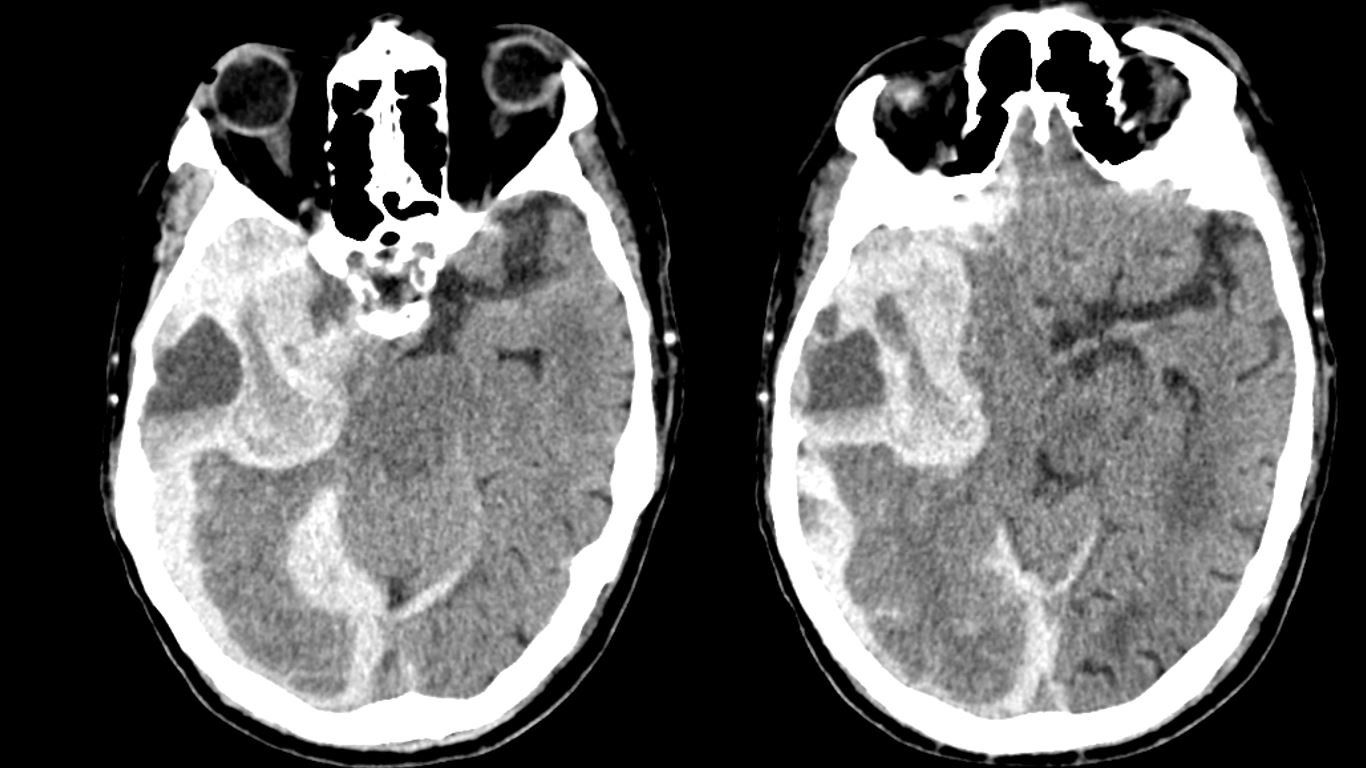

Ultimate Radiology Acute Intracranial Hemorrhage With Blood fluid Level

https://4.bp.blogspot.com/-wEvdMDC-kic/WUljMDoa8kI/AAAAAAAAC84/UaCtLkRxTqM2HhMosIcLFK_jQpBDnK-ZACLcBGAs/s1600/hemorrhage%2Bwith%2Bfluid%2Blevel.JPG